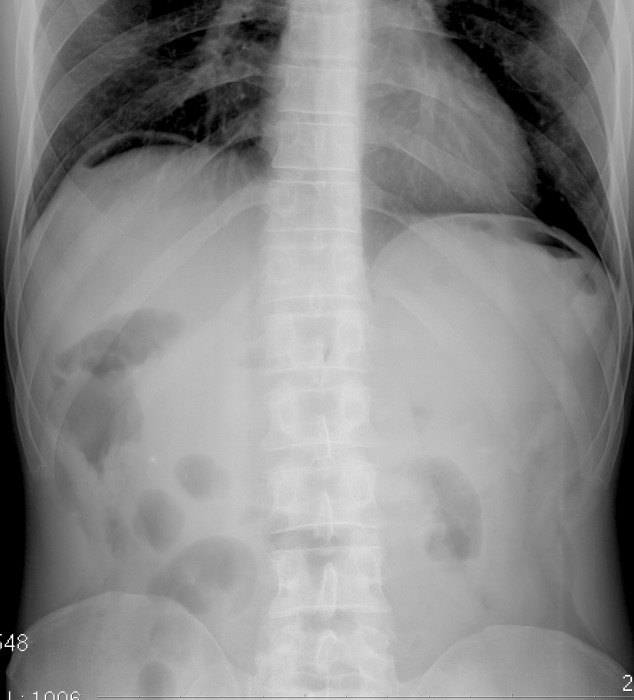

Нормы обзорной рентгенографии брюшной полости